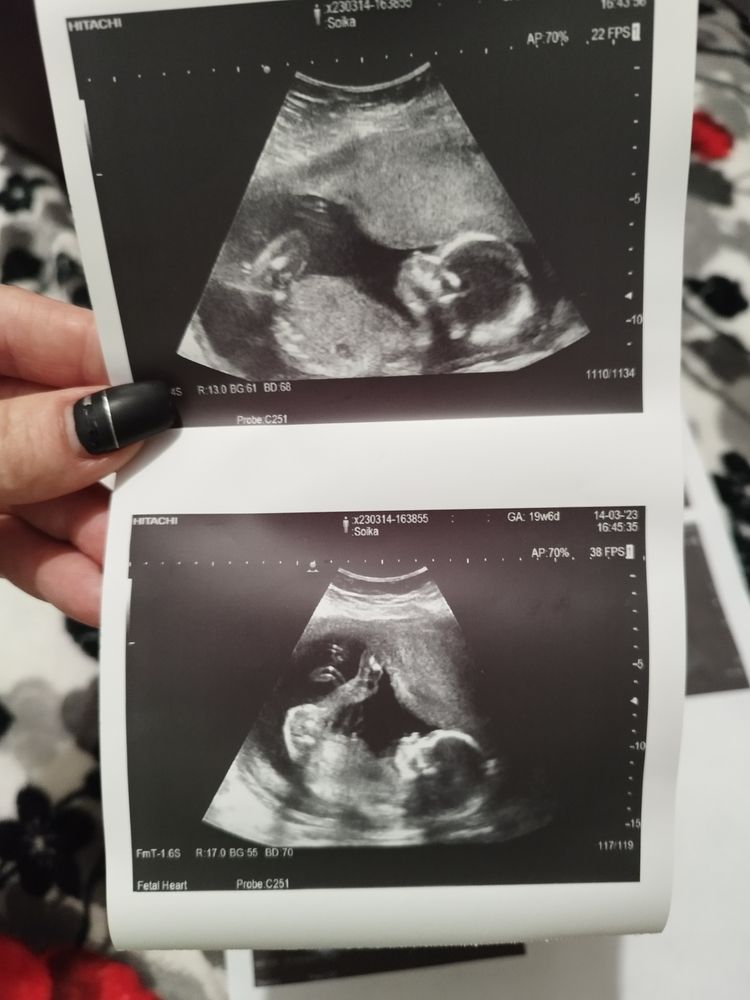

Как думаете кто

Пол малышаПол мы пока не узнаём, через неделю гендер пати...

Но все равно,как думаете кто?? Видно что нибудь?

На первом и последнем фото ножки достаточно высоко подняты должны были быть видны яички , если б был мальчик, так что я думаю 👧